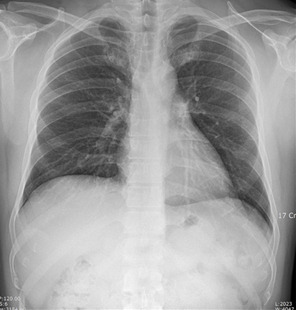

흉부 X-ray는 폐, 심장, 늑골, 종격동 등 가슴 안의 구조를 전반적으로 살펴보는 기본 영상 검사입니다. 주 목적은 폐렴, 결핵, 종양 같은 폐 질환의 가능성을 선별하고, 심장의 크기나 모양에 이상이 없는지를 확인하는 데 있습니다. 중요한 점은 흉부 X-ray가 ‘확진 검사’가 아니라 ‘선별 검사’라는 사실입니다. 작은 변화나 애매한 그림자도 놓치지 않기 위해 다소 보수적으로 판독되는 경우가 많습니다. 이 때문에 실제 임상적으로 의미 없는 소견도 결과지에 함께 기재될 수 있습니다.

‘음영 증가’라는 표현은 X-ray 사진에서 특정 부위가 주변보다 더 뿌옇게 보인다는 뜻입니다. 이는 염증, 과거의 흉터, 자세나 호흡 상태에 따른 일시적 변화 등 다양한 원인으로 나타날 수 있습니다. 이 표현 자체가 곧바로 질병을 의미하는 것은 아닙니다. 특히 증상이 없고, 이전 검사와 비교해 변화가 없다면 과거 병변이나 해석상의 차이일 가능성도 큽니다. 그래서 ‘추적 관찰’이라는 말과 함께 적히는 경우가 많습니다.

‘침윤’이라는 단어는 염증이나 체액 등이 조직에 스며든 상태를 의미합니다. 흉부 X-ray에서는 폐렴 초기나 회복 과정에서도 이런 표현이 사용될 수 있습니다. 경미한 침윤이나 염증 소견은 반드시 치료가 필요한 상태라기보다, 최근 감기나 호흡기 감염의 흔적일 수도 있습니다. 증상이 없거나 이미 호전된 상태라면, 경과 관찰만으로 충분한 경우도 많습니다.

이 표현은 현재 진행 중인 질환보다는, 예전에 있었던 변화의 흔적일 가능성을 시사합니다. 과거 결핵, 폐렴, 염증 후 흉터 등이 이런 식으로 표현될 수 있습니다. 과거 병변 의심이라는 문구는 ‘지금 당장 문제’라는 의미가 아니라, “이런 흔적이 보인다”는 기록에 가깝습니다. 이전 X-ray와 비교했을 때 변화가 없다면, 임상적으로 큰 의미를 두지 않는 경우도 많습니다.